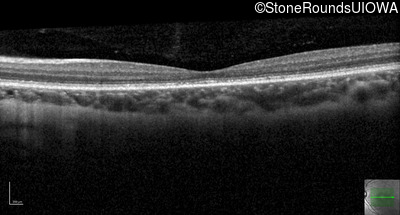

Optical Coherence Tomography - Left - 20/25 -2 sc

Exemplar / OCT Stack

OCT Stack